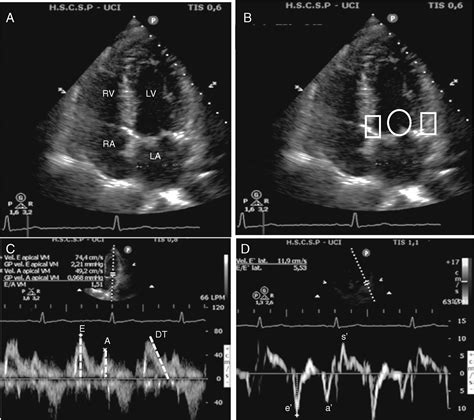

A physician usually diagnoses this condition through non-invasive imaging. The primary tool used is the echocardiogram, an ultrasound of the heart. During this test, a cardiologist uses Doppler imaging to measure the speed and pattern of blood flow into the left ventricle. In Grade 1, the echocardiogram typically shows a characteristic pattern where the "E-wave" (early filling) is lower than the "A-wave" (atrial contraction), indicating impaired relaxation.

This condition is often identified during an echocardiogram, where cardiologists observe how blood flows into the heart. It is frequently associated with aging, high blood pressure, or other cardiovascular risk factors. Because it is the mildest form of diastolic dysfunction, it is often considered a reversible or manageable condition if underlying causes are addressed promptly.